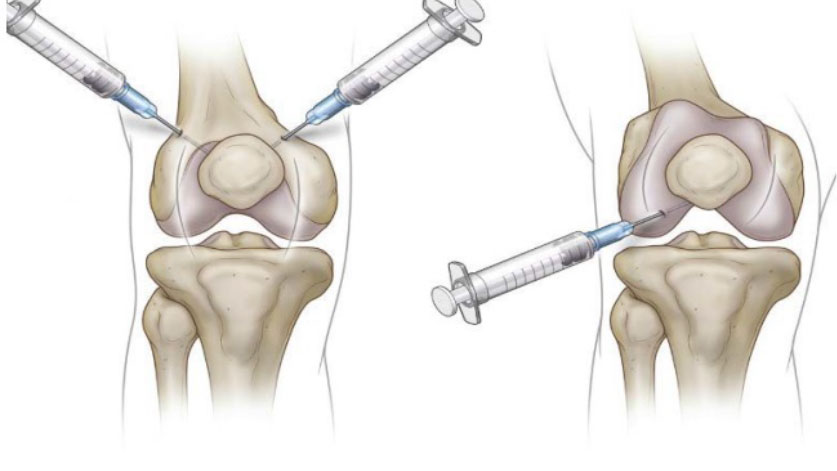

Ürün, 6-8-12 ay gibi tavsiye edilen sıklık kararına uygun olarak, hekim tarafından belirlenen sıklığa göre uygulanmalıdır. Enjeksiyon sayısı, sizin ve doktorunuzun kararıdır.

Tedavi her iki dizde aynı anda veya farklı zamanlarda olabilir. Bu uygulama için yalnızca ajanları eklem içi sinovyal eklem boşluklarına ulaştırmak için kabul edilen enjeksiyon teknikleri konusunda eğitimli tıp uzmanları sodyum hyalüronat enjekte etmelidir (Ortopedistler).